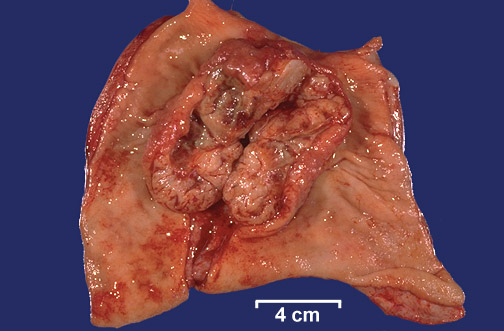

| The prominent mass seen here arose in the muscular wall of the stomach and grew exophytically toward the lumen, retaining a covering of mucosa except in the central ulcerated area. This is a gastrointestinal stromal tumor (GIST). These lesions used to be classified as smooth muscle tumors, but are now thought to arise from the interstitial cell of Cajal, a cell that forms part of the myenteric plexus. |